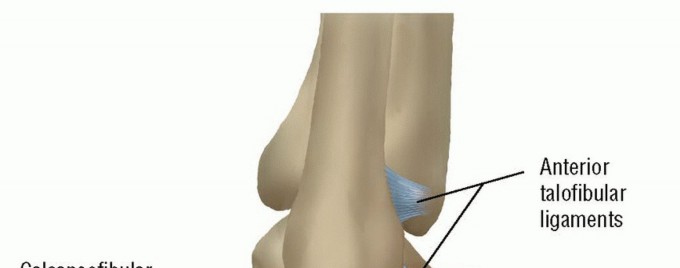

DEFINITION Lateral ligament instability occurs in some patients after an inversion injury.38 Although an inve…